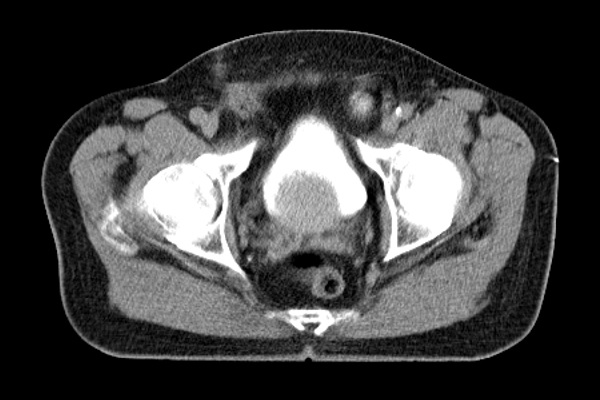

Radiotherapy planning software is responsible for generating contours for protection of risk organs and contours for tumor areas. To exemplify this process, below are the contours and radiations for you to interact with! Change the position of the slide (green circle) and check the outlines and rays (radiation) generated with SIPRAD for a radiotherapy treatment.

Generation of protective contours of risk organs and tumor areas.